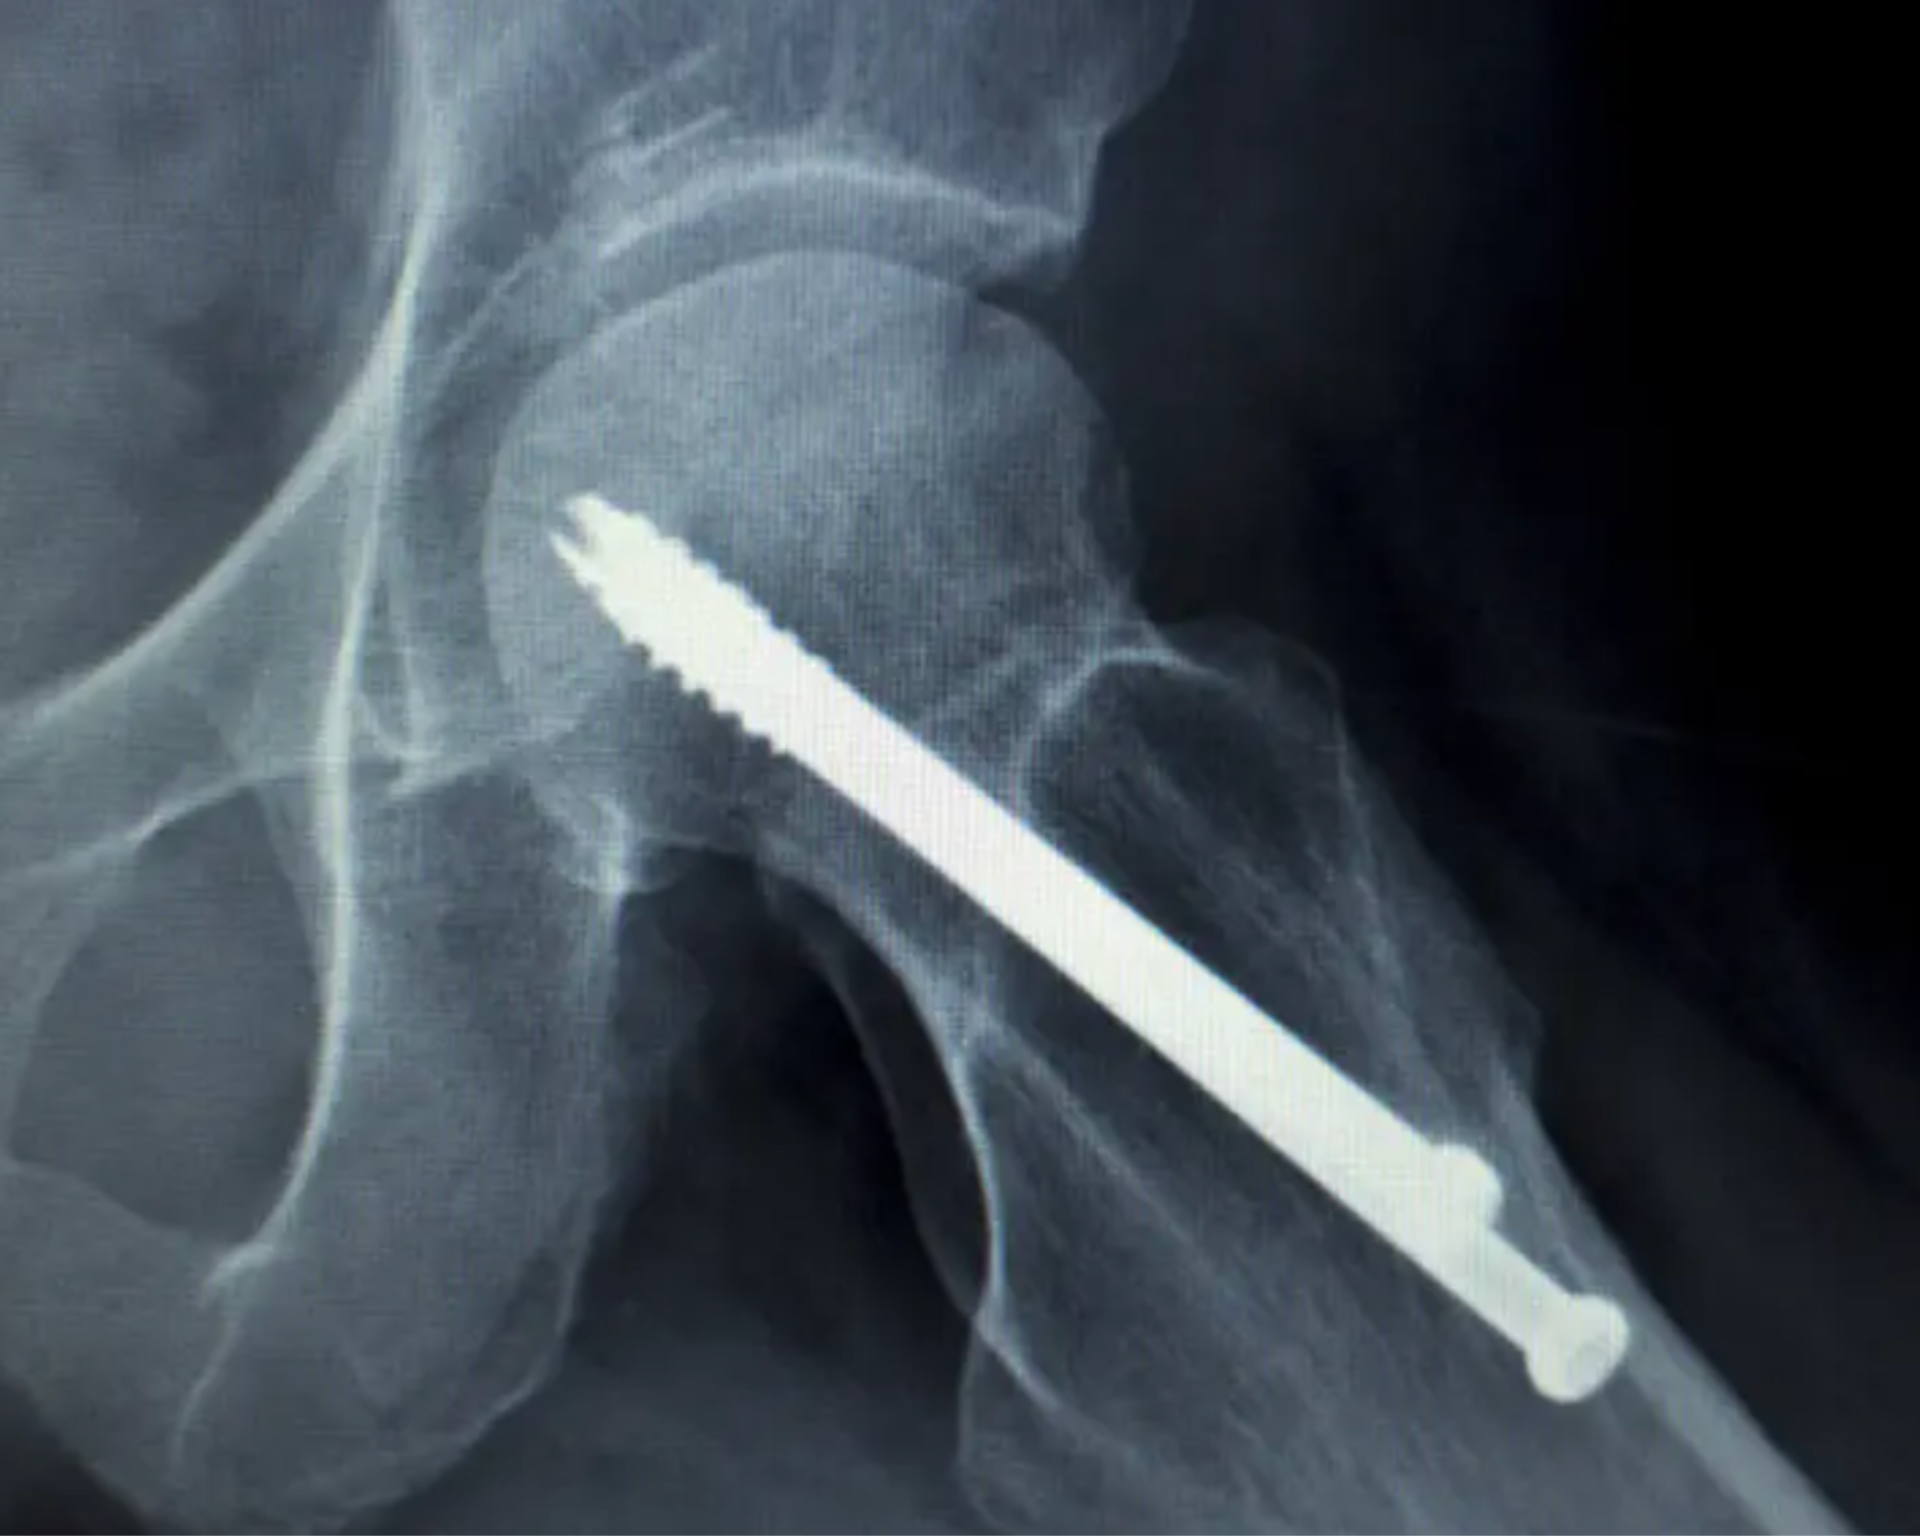

Tıbbi kaplama üreticileri, cerrahi alet tanımlamasını iyileştirmek ve ameliyathanedeki parlamayı azaltmak için uzun süredir fiziksel buhar biriktirme (PVD) kaplamaları kullanmaktadır. Günümüzde, aşınma direnci, alet ömrünü uzatma, antibakteriyel özellikler ve kayan bileşenler arasındaki sürtünmeyi azaltma gibi işlevsel kaplamalar bu pazarda hızla yaygınlaşmaktadır. PVD tıbbi kaplamalar ince, sert, pürüzsüz, biyouyumlu ve çok dayanıklı olabilir; bu da onları hassas cerrahi aletlerden yıllarca güvenle dayanması gereken yapay eklemlere kadar her şey için ideal hale getirir.